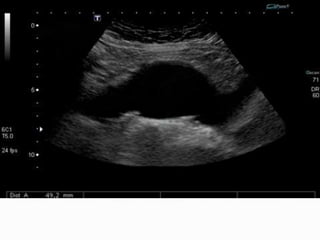

SONOGRAPHIC PRINCIPLES

 Maximum diameter is measured from outer edge of the wall

to outer edge of the opposite wall.

 Measurements should be taken perpendicular to the axis of

the lumen.

 With fusiform aneurysm measurement is taken in any

longitudinal plane.

 Transverse scanning is necessary for saccular aneurysm and

measurement is taken in the plane of eccentricity of

aneurysm.

 Completeness of the examination is assessed by seeing celiac

artery or aortic hiatus of diaphragm proximally and aortic

bifurcation distally.